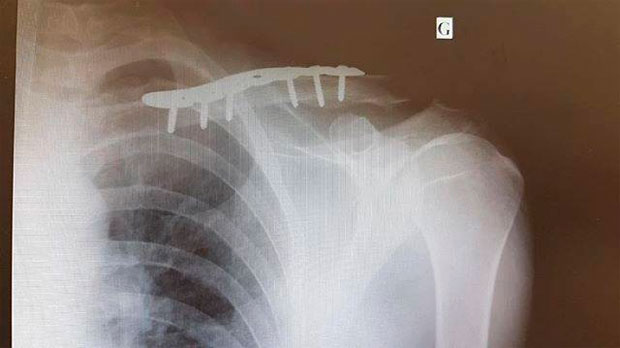

Como todo profesional de élite que se precie, la operación para reparar el hueso fue programada para la mañana del día siguiente, 2 de junio, con un resultado satisfactorio a costa de unos cuantos clavos metálicos fijados al hueso. ¿El tiempo de recuperación? Si no surgen problemas, aproximadamente tres semanas; lo justo para poder correr en la tercera cita de la Copa del Mundo XCO 2017, el 2 de julio en Vallnord (Andorra).